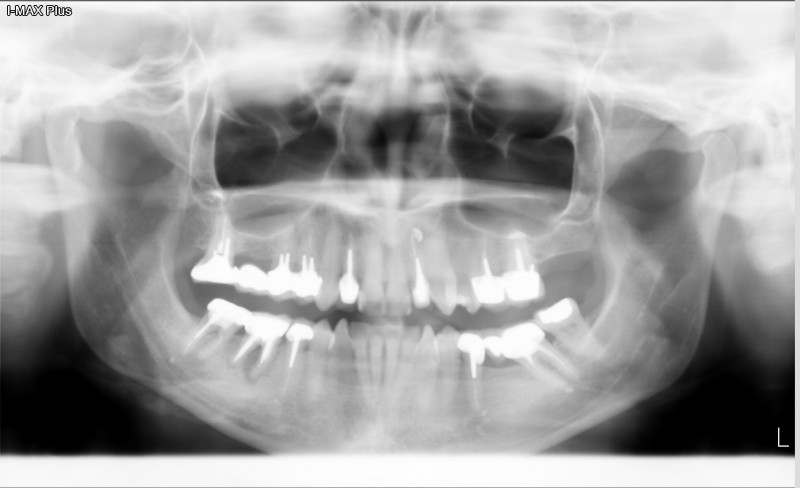

Les Terrasse de Bonneveine à Marseille, centre de radiologie, est ouvert du lundi au samedi pour des prestations d'imagerie médicale pour votre dentiste par exemple.